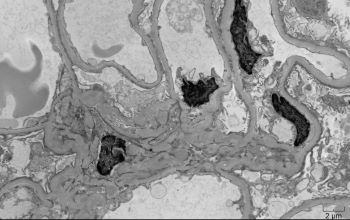

A 42-year-old African-American female with a history of systemic lupus erythematosus with acute kidney injury (creatinine 2.7 mg/dL), proteinuria (1064 mg/24 hr), and no hematuria, was admitted for lupus encephalitis. Renal biopsy by light microscopy showed that most glomeruli had no lesions (Figure 1) with one glomerulus with glomerular tuft collapse, and podocyte hypertrophy/hyperplasia (Figure 2). There was positive mesangial staining by immunofluorescence with IgG, IgM, IgA, C3, C1q, and light chains (Figure 3). Electron microscopy findings included diffuse foot process effacement, and mesangial electron-dense deposits (Figure 4).